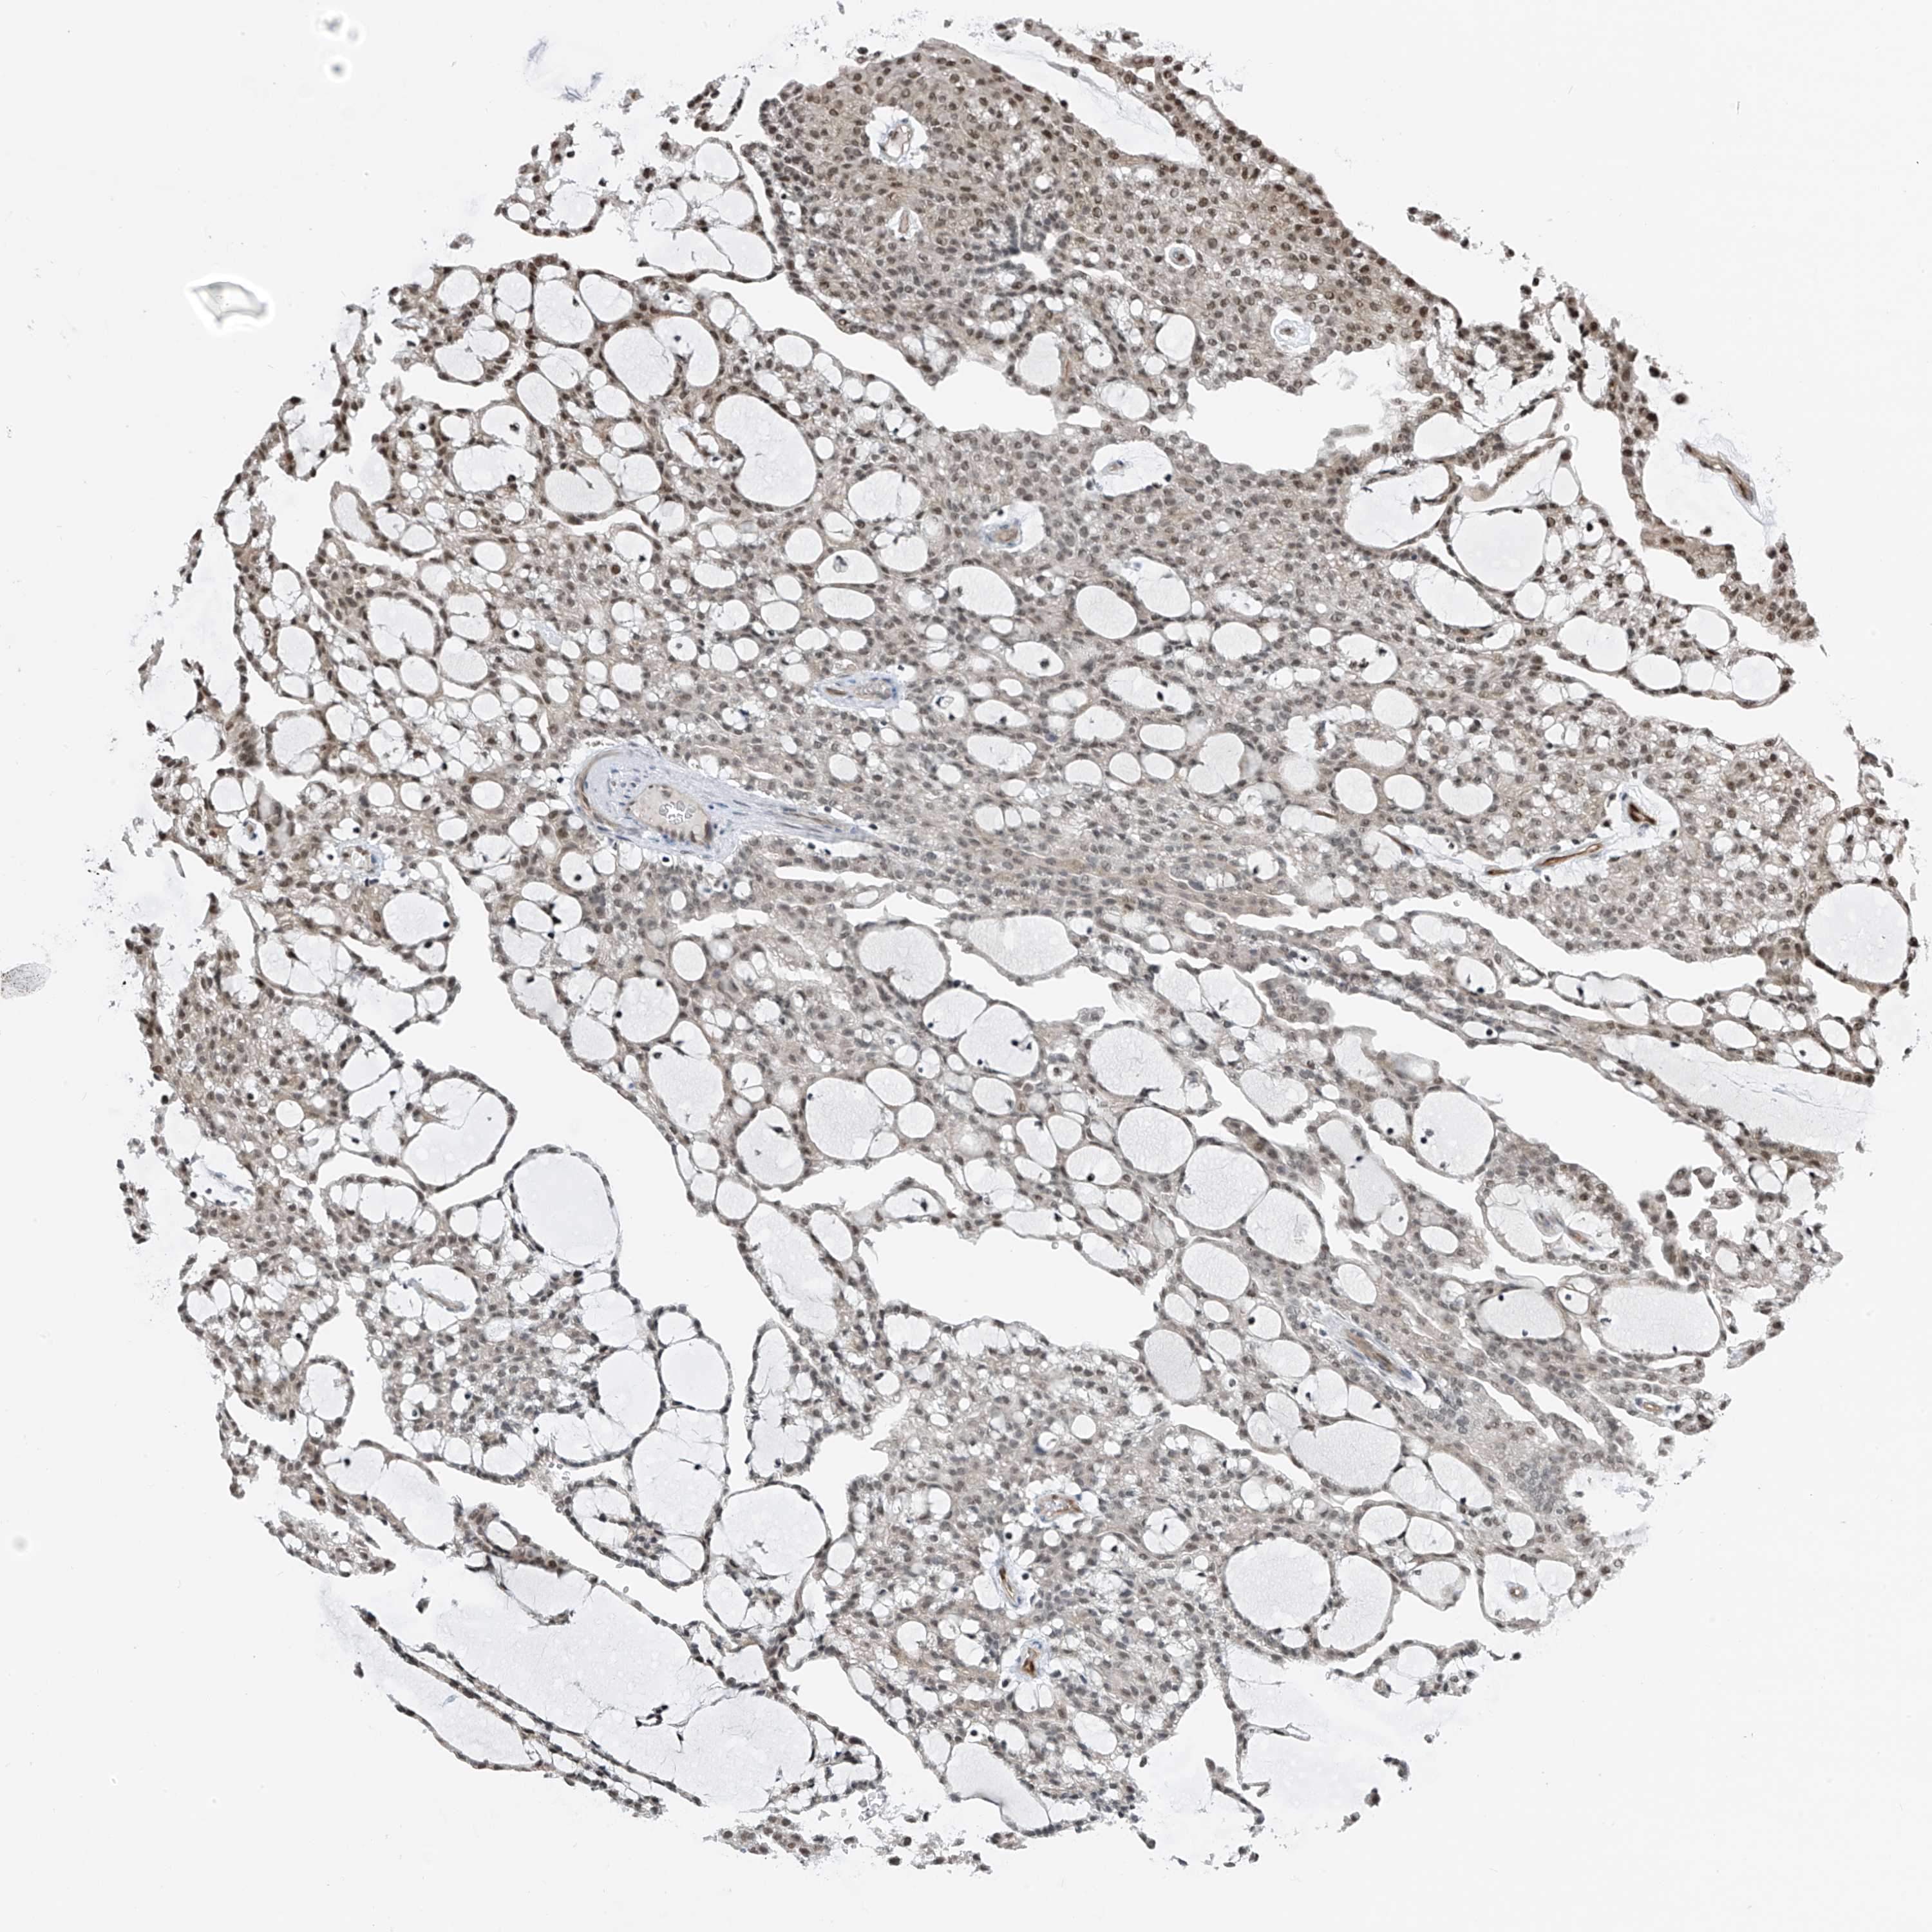

KIDNEY RENAL CLEAR CELL CARCINOMA (VALIDATION) - Interactive survival scatter ploti

The Survival Scatter plot shows the clinical status (i.e. dead or alive) for all individuals in the patient cohort, based on the same data that underlies the corresponding Kaplan-Meier plots. Patients that are alive at last time for follow-up are shown in blue and patients who have died during the study are shown in red.

The x-axis shows the expression levels (FPKM) of the investigated gene in the tumor tissue at the time of diagnosis. The y-axis shows the follow-up time after diagnosis (years). Both axes are complimented with kernel density curves demonstrating the data density over the axes. The top density plot shows the expression levels (FPKM) distribution among dead (red) and alive patients (blue). The right density plot shows the data density of the survived years of dead patients with high and low expression levels respectively, stratified using the cutoff indicated by the vertical dashed line through the Survival Scatter plot. This cutoff is automatically defined based on the FPKM cutoff that minimizes the p-score. The cutoff can be changed by dragging the vertical line or by entering a cutoff value in the square labeled "Current cut-off".

Under the Survival Scatter plot the p-score landscape (black curve; left axis) is shown together with dead median separation (red curve; right axis). Dead median separation is the difference in median mRNA expression between patients who have died with high and low expression, respectively. It is calculated as follows: median FPKM expression of dead patients with high expression - median FPKM expression of dead patients with low expression. This is intended to aid the user in visually exploring custom cutoffs and the associated p-scores and dead median separation.

Individual patient data is displayed and can be filtered by clicking on one or more of the category buttons on the top of the page. Categories describing expression level and patient information include: high, low, alive, dead, female, male and tumor stages. The scale of the x-axis can be toggled between linear and log-scale by clicking on the "x log" button. Mouse-over function shows TCGA ID, patient information and mRNA expression (FPKM) for each patient.

& Survival analysisi

Kaplan-Meier plots summarize results from analysis of correlation between mRNA expression level and patient survival. Patients were divided based on level of expression into one of the two groups "low" (under cut off) or "high" (over cut off). X-axis shows time for survival (years) and y-axis shows the probability of survival, where 1.0 corresponds to 100 percent.

RBP7 is validated prognostic, high expression is favorable in Kidney Renal Clear Cell Carcinoma (validation)

: 43.39

Average pTPM 64.7

Number of samples 100